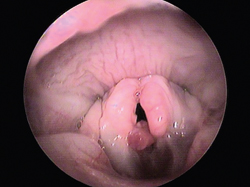

4. Ceruminous Gland Adenomas

These are unique tumors of the inner surface of the pinna and the external ear canal and arise from the cerumen glands (Figure 8A).

Ceruminous Gland Adenomas

Figure 8A

Although the tumors are benign, they are unsightly and obstruct the flow of air in the external ear canal, resulting in chronic otitis externa. The CO2 can easily vaporize the masses (Figure 8B). When healing is complete, the ear appears normal (Figure 8C). Unfortunately, affected cats form new masses over six to 15 months, so repeat therapy will be needed.

Figure 8B

Figure 8C